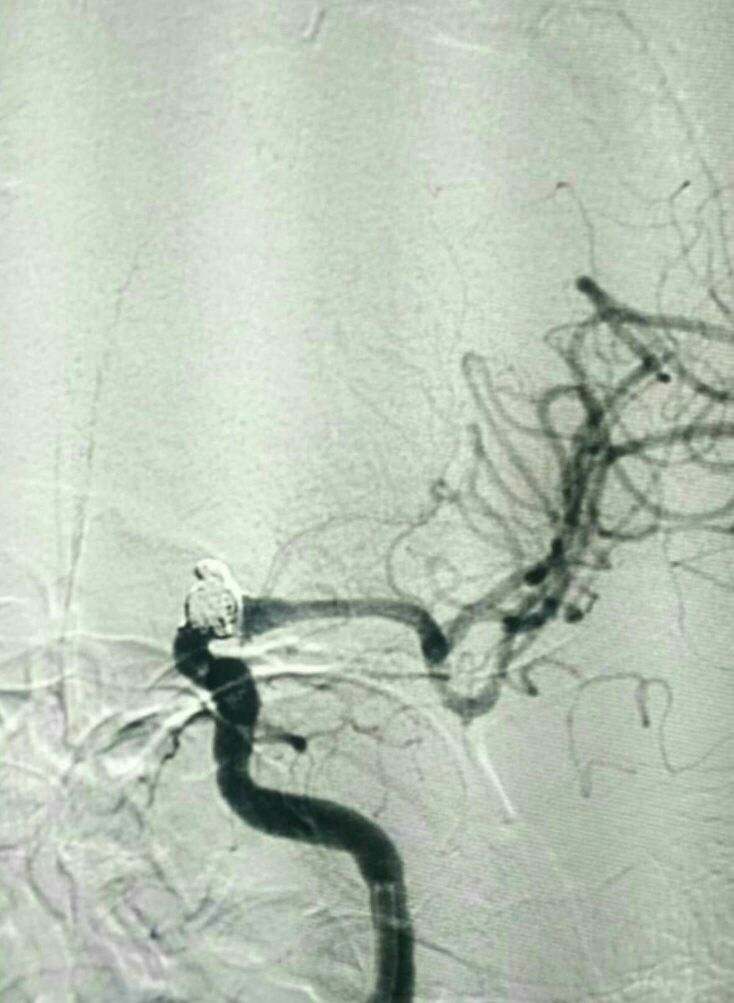

DSA左侧ICA“血泡”样动脉瘤

动脉瘤大小5.5*8mm

手术方案:双支架+弹簧圈+打补定致密栓塞

栓塞工作角度33/-28影像满意